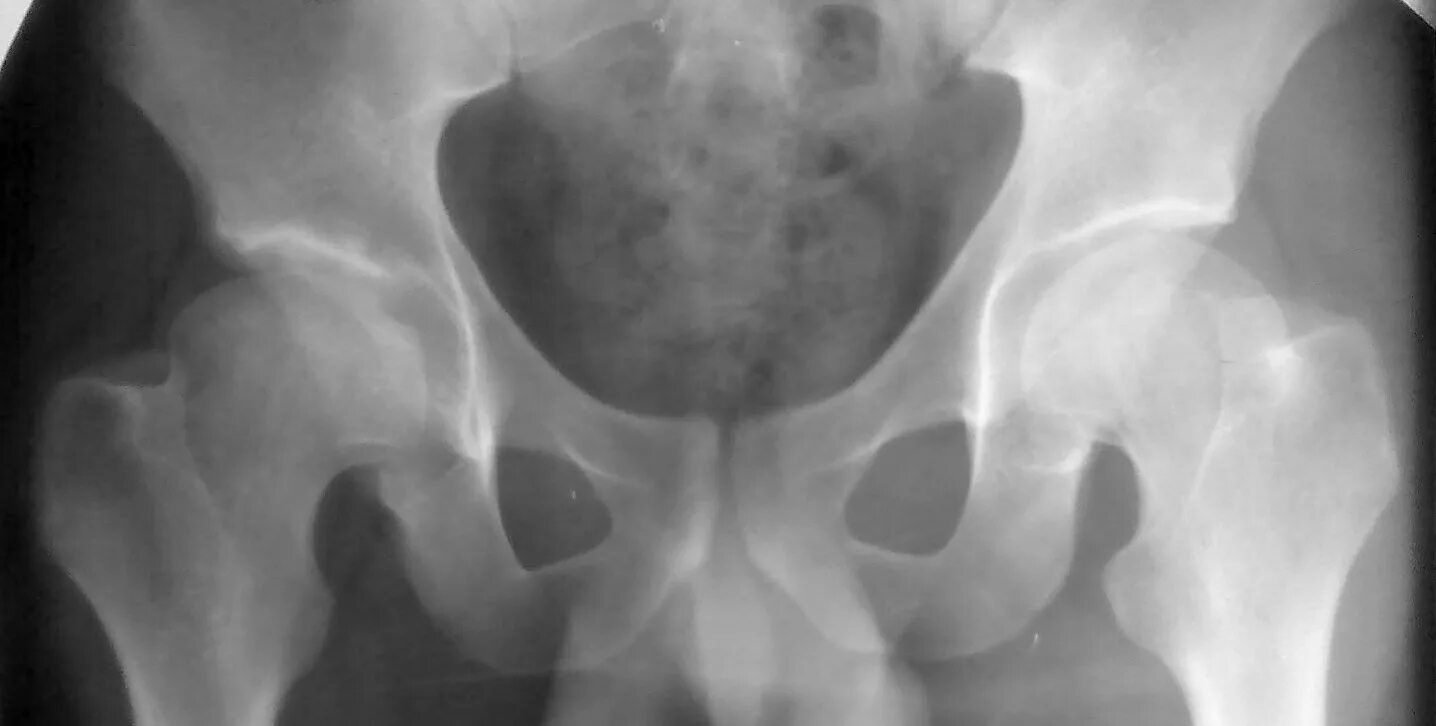

Артрит тазобедренного сустава симптомы